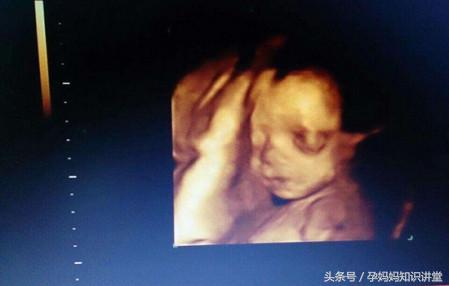

8、为了避免做彩超时宝宝的位置不好而照不到脸部细节,所以孕妈做排畸前应多动动散散步,这样有利于宝宝的胎位达到最佳位置。